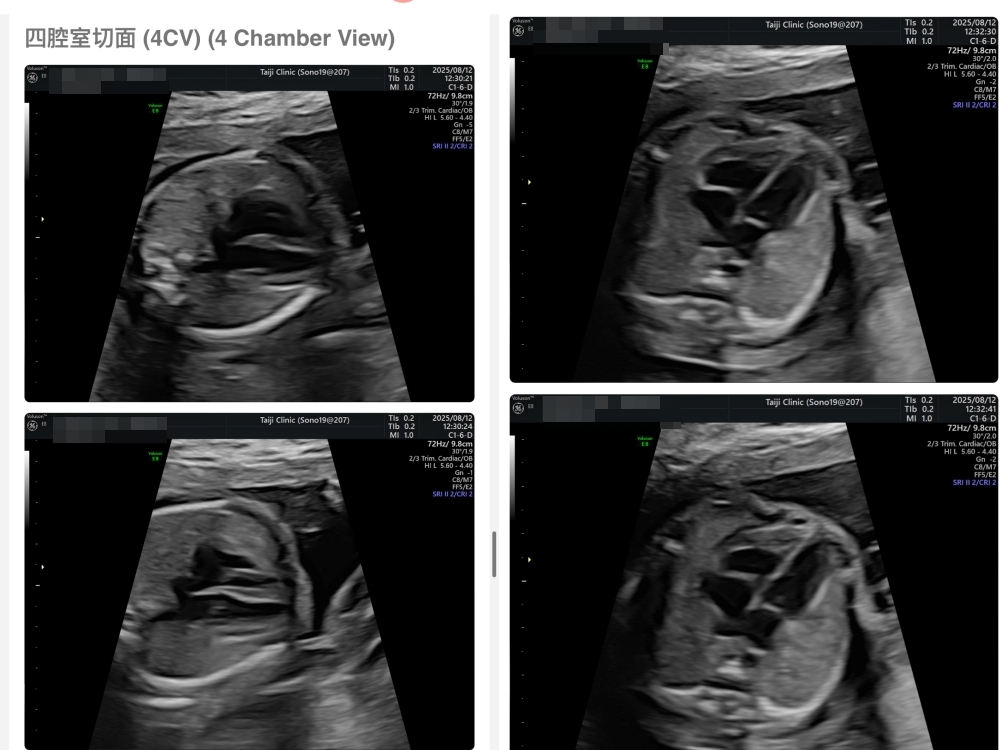

【台兒|高層次超音波|檢查結果】

▲離開診所後會收到MAIL,我們14:05離開,大約是16:45收到mail,裡面會有滿滿的超音波照片,紀錄的很詳細!也會提供紙本的報告,可以給日後產檢的醫師做參考👌